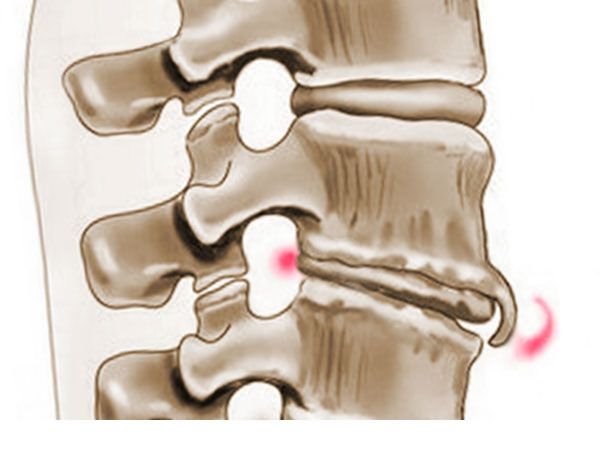

Для такой патологии, как спондилёз, характерно отслоение связочного аппарата от тел позвонков и формирование остеофитов на месте этого самого отслоения. Болезнь прогрессирующая. Процесс окостенения на месте отслоения, по-другому – оссификация, постепенно нарастает и приводит к образованию костных мыщелков в форме дуги. Уменьшается высота стояния межпозвоночных дисков. Спондилёз характерен для людей пожилого возраста. Неудивительно, что наряду с нарушениями дегенеративно-дистрофического характера в патогенезе наблюдаются инволюционные процессы. Болезнь может встречаться и у более молодых представителей мужского пола, особенно у тех, чья активная деятельность связана с постоянным поднятием тяжестей.

При спондилёзе, в отличие от спондилоартроза, поражаются только межпозвоночные диски. Это приводит к образованию остеофитов. При спондилоартрозе поражаются все структуры мелких межпозвоночных суставов. При спондилёзе остеофиты разрастаются в межпозвоночных отверстиях, что способствует сужению вертебрального канала. А при спондилоартрозе разрастание отмечается по краям мелких суставов.